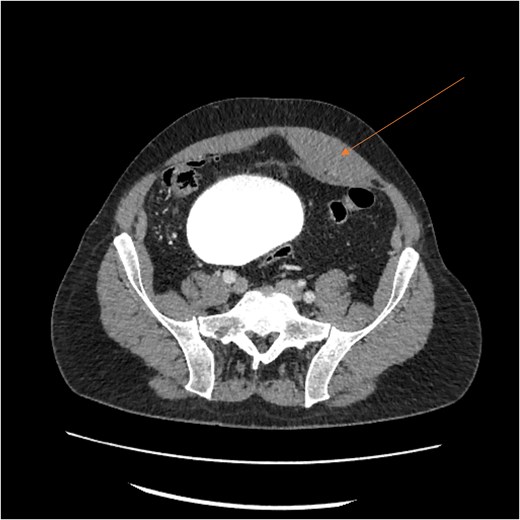

A follow-up CT scan performed 2 days after placement of IVC filter and stopping anticoagulation showed further enlargement of the hematoma (17.5 × 14 × 25.7 cm) and ongoing bleeding. Interventional radiology performed bilateral inferior epigastric artery angiograms, which revealed no ongoing artery bleeding but truncation of the right inferior epigastric artery. Empiric Gelfoam embolization was performed on the left inferior epigastric artery (Fig. 4).

Angiogram of the left inferior epigastric artery (arrow) demonstrating no active bleeding.